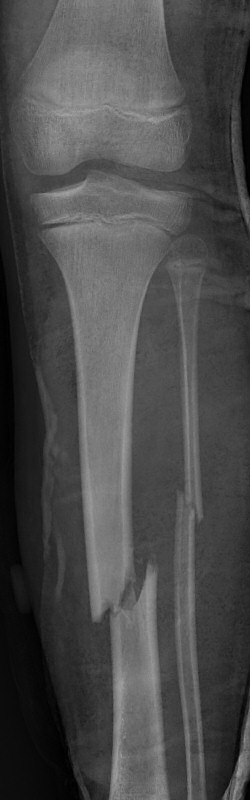

Tibia och fibula-frakturer, tibia spikats med 2 TEN-spik, sista 2 bilderna efter 5 veckor, då inte alls ömmande över frakturerna.